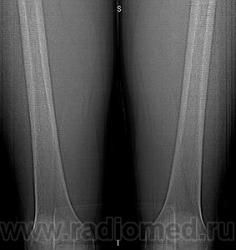

Молодой человек, спортсмен, профессионально занимается футболом с вытекающими последствиями, был обследован на МРТ ,область т/бедренного сустава, в диафизе обнаружилась якобы киста, направлен на КТ. Результаты КТ:

Публикации: 16

Молодой человек, профессионально занимается футболом, был обследован на МРТ по поводу травмы тазобедренного сустава. Со стороны сустава грубой патологии не выявлено, но в диафизе бедренной кости обнаружили якобы кисту. Был обследован на КТ. Ваше мнение?

Эностальная реакция или отколы мелких фрагменов костной ткани изнутри?

При биопсии оказалась хондросаркома. Боли в этой области не беспокоили. "Зазубрина" на контуре кости при реконструкции-артефакт в результате движения конечности.

По КТ картине было высказано предположение в дифференциальном ряду, но для нас, честно говоря, биопсия была полной неожиданностью.